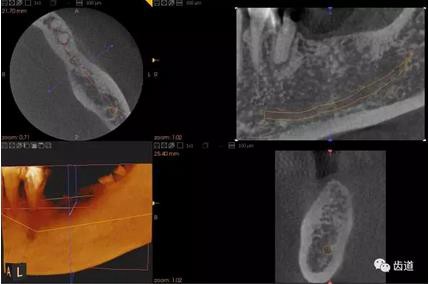

三)種植修復(fù)

CBCT在牙種植修復(fù)中的應(yīng)用。種植前利用CBCT對患者的牙床進行檢查,可精準(zhǔn)判斷牙槽骨的寬度、厚度及高度、骨的密度、重要的顏面神經(jīng)、血管和鼻竇位置等。臨床醫(yī)生不僅可以在計算機直觀的看到牙槽骨的立體影像,還可以切換不同的視角來觀察硬組織之間的位置關(guān)系,在手術(shù)方案中避開危險區(qū)域,保證手術(shù)的安全性。臨床醫(yī)生還可以利用CT數(shù)據(jù)進行數(shù)字模型重建,配合軟件預(yù)先做好手術(shù)模板,使種植手術(shù)更安全快捷,避免在種植手術(shù)過程中不慎破壞神經(jīng)、鼻竇等解剖結(jié)構(gòu),導(dǎo)致顏面神經(jīng)麻痹、鼻竇炎等并發(fā)癥的發(fā)生。

1、下頜骨種植牙前測量準(zhǔn)備影像

2、上頜骨種植牙前準(zhǔn)備影像

3、下頜骨種植牙術(shù)后